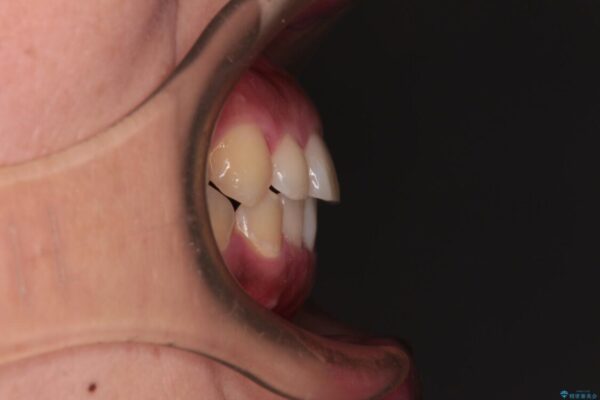

前歯の叢生と八重歯を気にして来院された患者様です。

治療前

• 【モニター】カリエール・ディスタライザーを併用した八重歯のインビザライン矯正 治療前画像